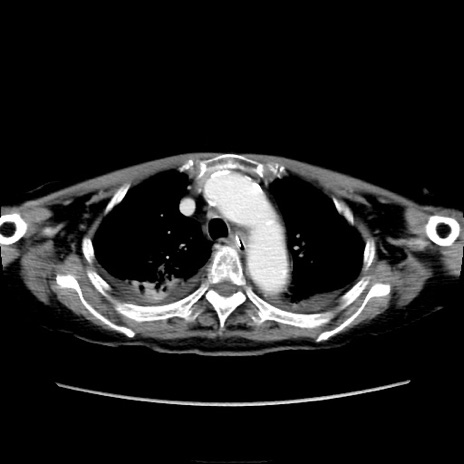

症例40(横断像)

【症例】90歳代女性

【主訴】腹痛・嘔吐

【現病歴】 食欲低下、嘔吐があり昨日他院受診。肺炎と診断され入院となる。入院後より腹部全体に圧痛あり。胃管留置され経過みていたが、症状持続するため、

当院転院となる。

【既往歴】胸椎圧迫骨折、胆石症

【身体所見】腹部:中央に激痛あり、圧痛あり、反跳痛不明

【データ】WBC 17100、CRP 18.82

他院CT

横断像